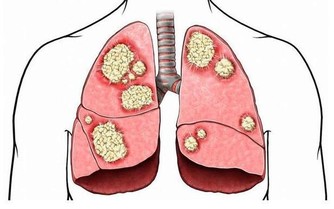

現在很多的年輕男性為了工作常應付多種應酬,在應酬中會經常大量的吸菸喝酒,長期吸菸對肺部會造成嚴重的損傷,容易誘發肺炎。所以經常吸菸的男性應該最好是戒菸,如一時戒不了煙,平時應該多吃一些能夠清肺的食物來保養肺部。